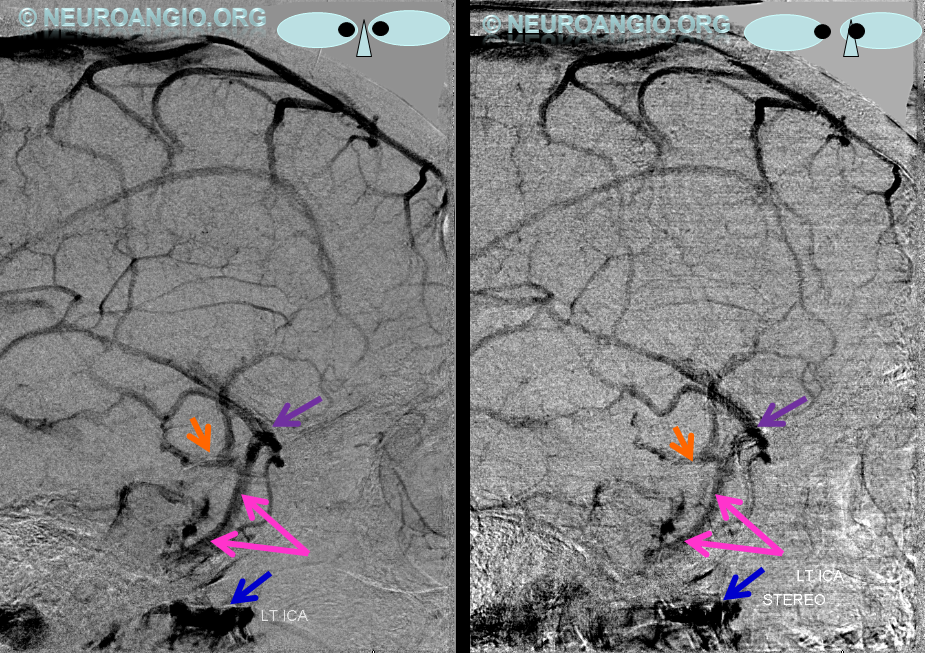

The general neurosurgical fact that the anterior third of the superior sagittal sinus can be safely sacrificed is true almost all the time. When it is not, consequences can be catastrophic. Normally, few veins drain into the anterior 3rd of the SSS, and these usually have collaterals. However, occasionally a large frontal or sylvian vein happens to drain anteriorly. Taking this sinus means risking a venous infarct. Here is an extreme example of dominant inferior left frontal vein draining into the anterior third of the frontal sinus, on MRI. Case courtesy Dr. Howard Riina

Angio is much easier to appreciate. It is well to learn how to spot these veins on MR or CT, as most patients don’t get presurgical angiography for nonvascular lesion

Anaglyph stereo